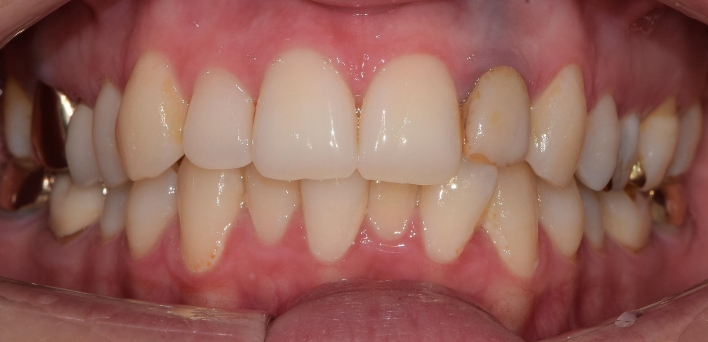

임플란트 : 손 ** 님 (50대)

치아가 있다는게, 아직도 정말 꿈만 같아요.

Before Before

2020.02.30

After After

※ 더서울치과의원은 의료법을 준수하며 위 케이스는 실제 환자의 동의를 얻은 사례로 치료 전, 후가 동일한 환경에서 촬영되었습니다.

환자 케이스에 따라 부작용이 발생할 수 있습니다. 이 부분은 의료진의 충분한 상담과 체크를 통해 예방하고 줄일 수 있습니다.

[임플란트 부작용] 수술 후 관리가 소홀할 경우 출혈, 주위염 등의 부작용이 발생할 수 있어 구강 위생을 철저히 유지하고, 정기적인 검진을 통해 상태를 점검하는 것이 중요합니다.

환자 특징

환자 특징01무치악 상태

환자 특징02수년간 무치악으로 지내심

임플란트가 불가능할것이라

생각하고 내원

위, 아래 6개씩 식립

디지털 풀아치 임플란트